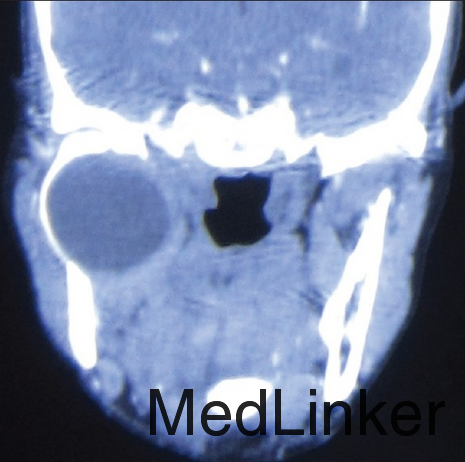

患者右侧颞下颌关节区开闭口和咀嚼吞咽轻度钝痛3年,要求治疗

检查发现面部对称,开口度正常,右侧颞下颌关节区可扪及柔软肿块,右侧颞下颌关节运动较左侧减弱,颈部淋巴结无明显肿大。 影像学检查发现右侧颞下颌关节可见一完整4.9*3.8cm大小溶骨性囊性病变,内含积液。